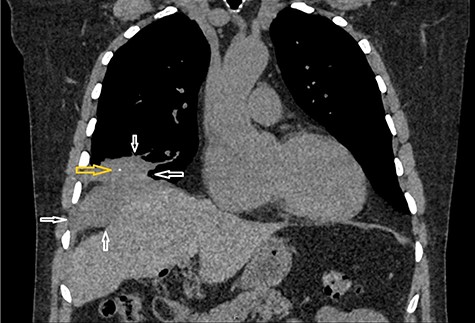

Incision and drainage of the back abscess were performed under general anaesthesia. Almost 200 mL of frank pus were drained, and after a washout, a corrugated drain was left in place. Also, during the procedure, a small gallstone was identified and removed (Fig. 4).

Image shows a small calculus removed during incision and drainage of the back abscess.